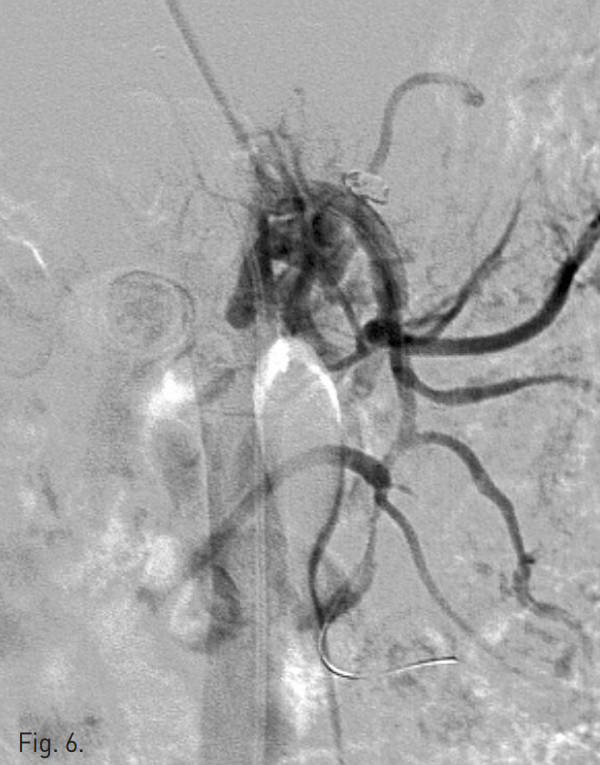

시술 후 시행한 상장간막동맥조영술상 dissecting aneurysm은 폐색되었고 상장간막동맥의 flow는 잘 유지되었다(Fig. 6). 시술 1주 후 시행한 CTA상 상장간막동맥의 벽내혈종은 그 양이 감소하였고, luminal narrowing은 호전되었으며, 동반된 합병증은 없었다(Fig. 7A, B).

Fig. 6

Immediately after intervention, SMA angiogram shows a good patent true lumen and ner completely embolized dissecting aneurysm.